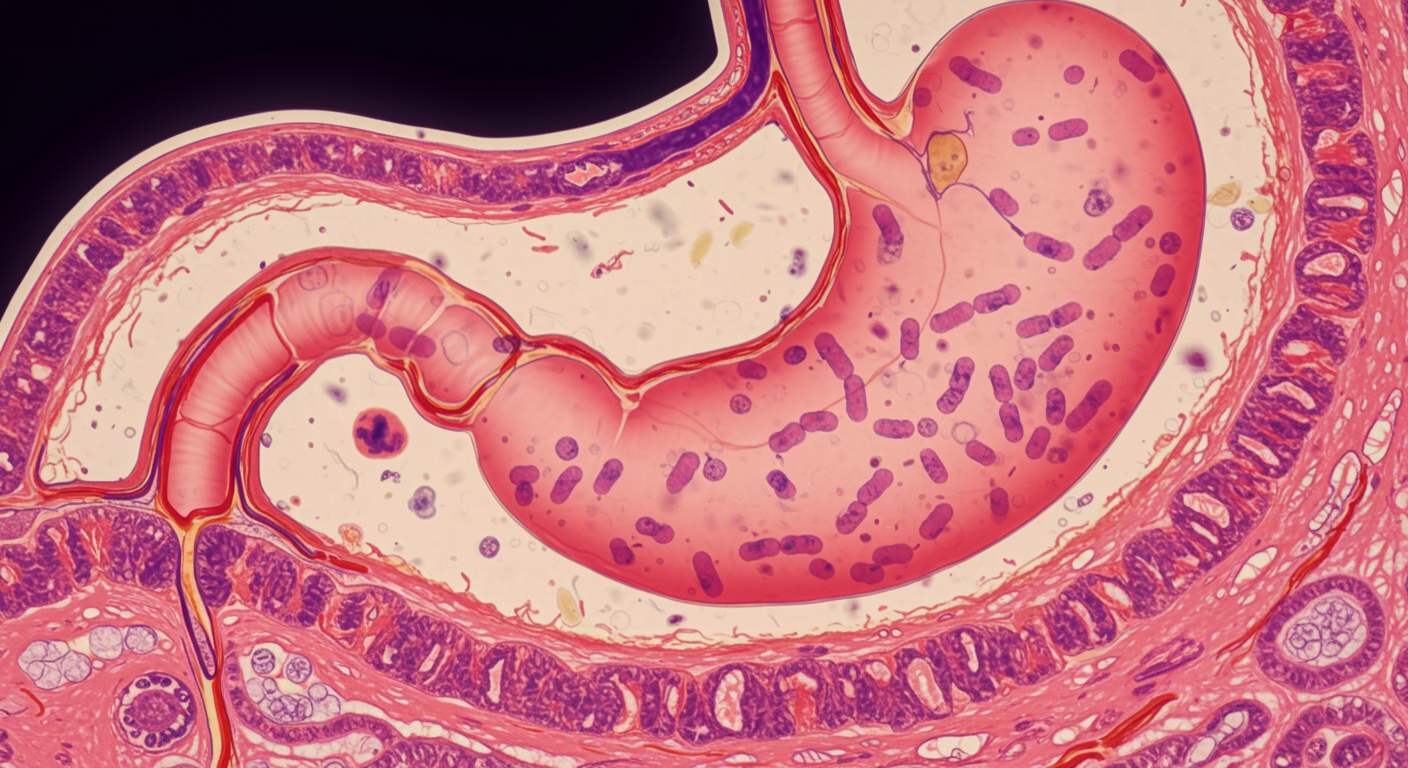

Does H. Pylori Infection Protect Against or Cause GERD?

The relationship between Helicobacter pylori and GERD is complex and paradoxical - H. pylori infection can both protect against and contribute to reflux disease depending on the bacterial strain, infection location, and individual host factors. This dual nature explains conflicting research findings and has important implications for treatment decisions in patients with both conditions.

H. pylori infection can protect against GERD by reducing gastric acid production through chronic gastritis and atrophic changes, particularly when the infection involves the gastric body. The bacteria can also produce ammonia and other compounds that buffer gastric acid.

However, H. pylori can worsen GERD when infection is limited to the gastric antrum, potentially increasing gastrin production and acid secretion. Certain virulent strains (CagA-positive) may also cause more severe inflammation that affects gastroesophageal junction function.